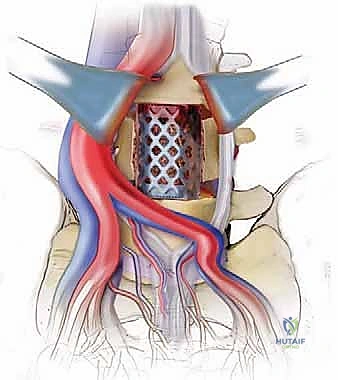

الخطوة 4: التحضير وزراعة القفص (Implant Insertion)

يتم قياس الفراغ المتبقي بدقة لاختيار الحجم المثالي للقفص الجراحي (Cage). يُصنع هذا القفص عادة من مادة PEEK أو التيتانيوم، ويتم حشوه بمادة عظمية (طعم عظمي ذاتي من المريض، أو طعم صناعي، أو بروتينات محفزة لنمو العظم BMP). يتم إدخال القفص بقوة في الفراغ، مما يؤدي فوراً إلى استعادة ارتفاع القرص الطبيعي وتوسيع المخارج العصبية (تخفيف الضغط غير المباشر).

الخطوة 5: التثبيت (Fixation)

لضمان أقصى درجات الثبات والسماح للعظم بالاندماج بمرور الوقت، يتم تثبيت القفص باستخدام شريحة معدنية صغيرة ومسامير من التيتانيوم تُثبت في الأجسام الفقرية من الأمام. في بعض الحالات، قد يرى الدكتور هطيف ضرورة إضافة تثبيت خلفي بمسامير عبر الجلد (Percutaneous Pedicle Screws) لزيادة الدعم.